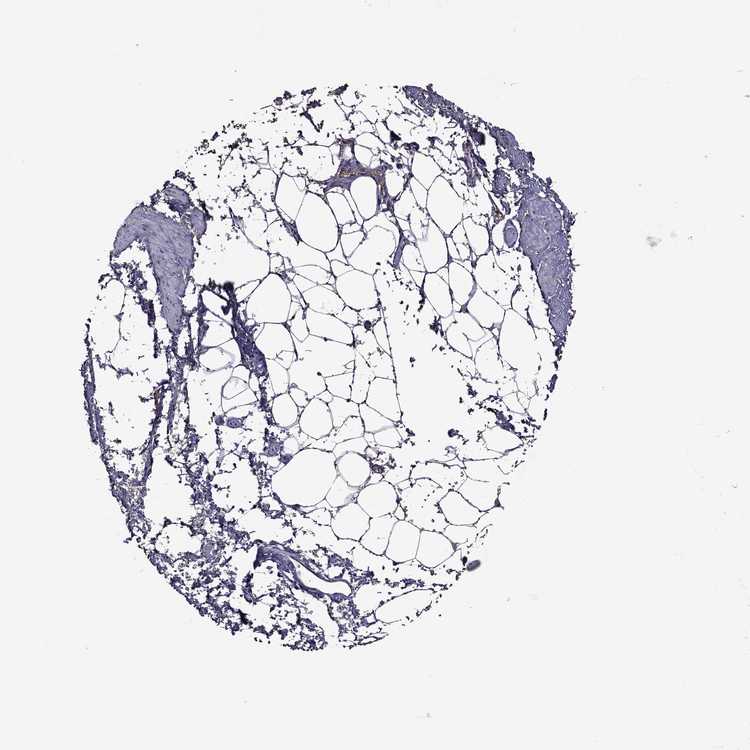

SOFT TISSUE 2 - Antibody stainingi

Antibody staining in the annotated cell types in the current human tissue is reported as not detected, low, medium, or high, based on conventional immunohistochemistry profiling in selected tissues. This score is based on the combination of the staining intensity and fraction of stained cells.

Each image is clickable and will lead to virtual microscopy that enables deeper exploration of all samples and also displays staining intensity scores, fraction scores and subcellular localization as well as patient and tissue information for each sample.

Antibody HPA078846

Fibroblasts Not detected